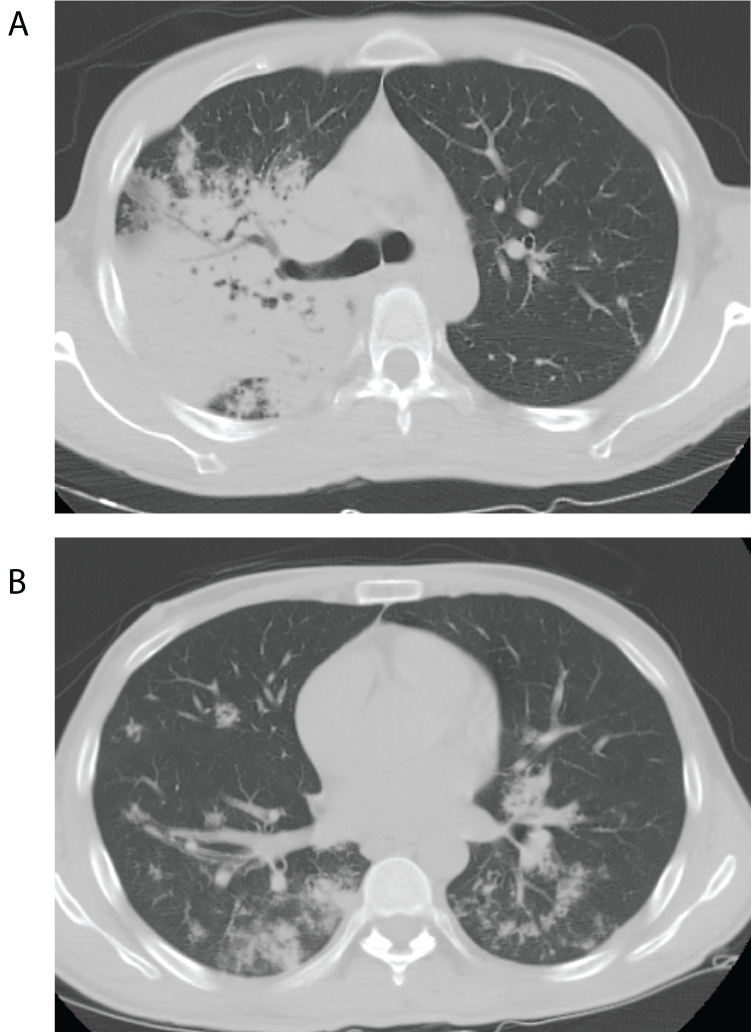

A young 32 year old Hispanic man presented with 4-weeks history of polyuria, polyphagia and weight loss and 2-weeks history of hemoptysis and shortness of breath. He denied fever, chills, night sweats, sick contacts, skin rash, glandular swelling or recent travel. He was a farmer who had emigrated from Mexico to New York City over a year ago and was currently working at a local grocery store. He denied any prior history of pulmonary symptoms. On examination the patient was cachectic, febrile, tachycardic and tachypneic and in respiratory distress. There were bronchial breath sounds in the right infraclavicular area. Laboratory investigations revealed mild leukocytosis and diabetic ketoacidosis (DKA). The chest X-ray (Figure 1) showed a dense right upper lobe infiltrate with bronchiectasis. A chest computed tomography (CT) (Figure 2) showed cavitary consolidation of the right upper lobe with patchy infiltrates in the right and left lower lobes.

Figure 1: Chest radiograph showing right upper lobe consolidation and

retraction of horizntal fissure.

Figure 2: (A) Representative image of Chest CT showing dense consolidation

of the right upper lobe. (B) Represenattive image of Chest CT showing

bilateral patchy lower lobe infiltrates.